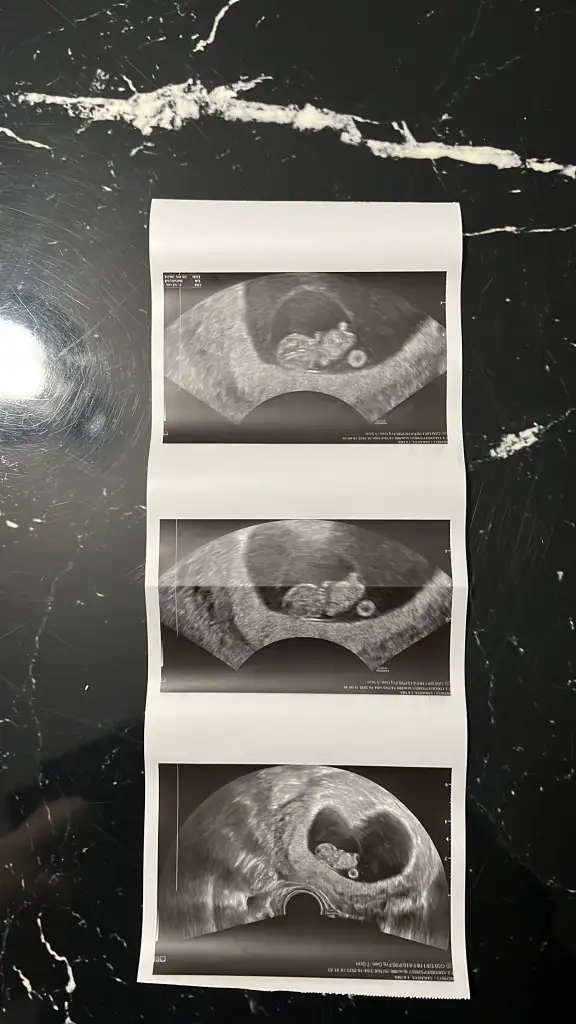

Kız bence. Ama tabiki her şeyin hayırlısı olsun. Şimdi koz diye kodlama. İllaki öğreneceksin.Burda 14 hafta 6gunluk du 92.2m ölçtü yer

Sağlıkla gelsinBugün ki ultrason fotoğrafı